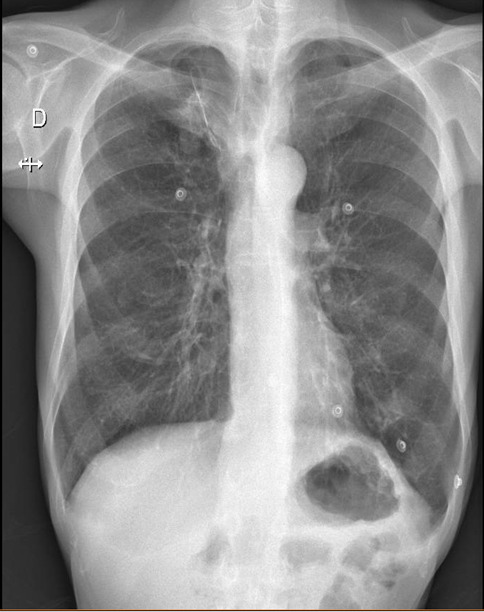

Diagnostic à évoquer systématiquement devant une toux chronique avec une exposition tabagique importante.

Diagnostic à évoquer systématiquement devant une toux chronique avec une exposition tabagique important.

Cause fréquente de toux chronique.

Les DDB sont des anomalies structurelles des bronches responsables d’une diminution de l’appareil mucociliaire responsable d’une toux chronique.